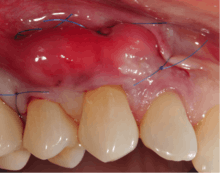

Technique

A small amount of blood (10 millilitres (0.35 imp fl oz; 0.34 US fl oz) per tube) is harvested and spun in a centrifuge for eight minutes at 1300 rpm. A fibrin clot packed with blood-derived growth factors, extra cellular matrix and hematopoietic stem cells is fabricated and implanted into the gums above the area of gum recession. Advanced platelet-rich fibrin will promote the patient's own gums to fabricate more gum thus eliminating the need to harvest gums from the roof of the mouth or the use of allografting tissue.

Following this procedure, patients require less recovery time due to enhanced healing factors. And improve quality.[8][9][10][11]

A free gingival graft is a dental procedure where a small layer of tissue is removed from the palate of the patient's mouth and then relocated to the site of gum recession. It is sutured (stitched) into place and will serve to protect the exposed root as living tissue. The donor site will heal over a period of time without damage. This procedure is often used to increase the thickness of very thin gum tissue.

A subepithelial connective tissue graft takes tissue from under healthy gum tissue in the palate, which may be placed at the area of gum recession. This procedure has the advantage of excellent predictability of root coverage,[12] as well as decreased pain at the palatal donor site compared to the free gingival graft. The subepithelial connective tissue graft is a very common procedure for covering exposed roots.